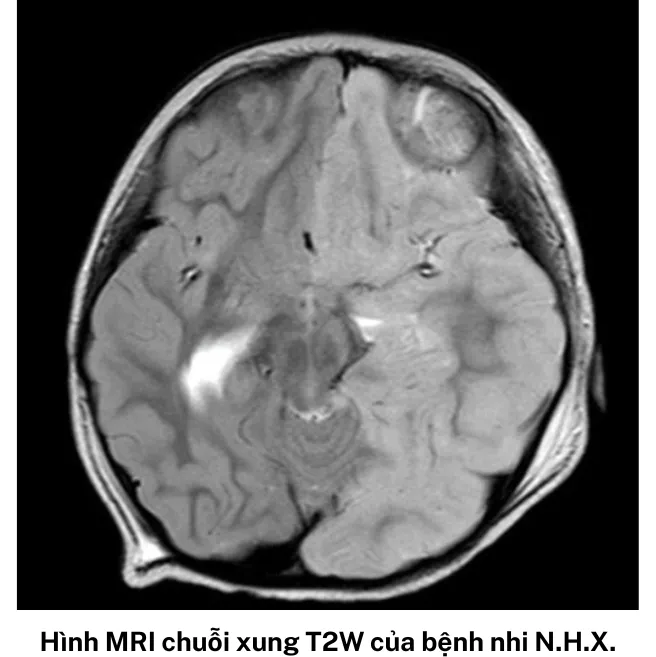

Kết quả MRI sọ não của bé X. cũng cho thấy có tổn thương kèm phù não gần như toàn bộ nửa bán cầu trái, đẩy lệch đường giữa sang phải, bán cầu não phải bị ép xẹp. Các bác sĩ của khoa nhanh chóng hội chẩn và sử dụng steroid liều cao 30mg/kg/ngày trong 5 ngày, đồng thời dùng kháng thể Globulin 1gram/kg/ngày truyền tĩnh mạch trong 2 ngày.

“Bệnh HHE được chẩn đoán xác định dựa vào hình ảnh học não đặc trưng trên MRI. Trong giai đoạn cấp tính có biểu hiện tổn thương phù nề nửa bán cầu não, tiếp đến là teo não không tương quan với bất kỳ vùng mạch máu nào. Nguyên nhân và tác nhân hiện tại của bệnh vẫn chưa rõ ràng. Nhiều giả thuyết đặt ra có thể do miễn dịch và chuyển hóa”, bác sĩ Đỗ Châu Việt thông tin và cho biết, không chỉ là bệnh hiếm, người mắc hội chứng HHE thường tiên lượng xấu, di chứng thần kinh và khả năng kháng thuốc động kinh cao.